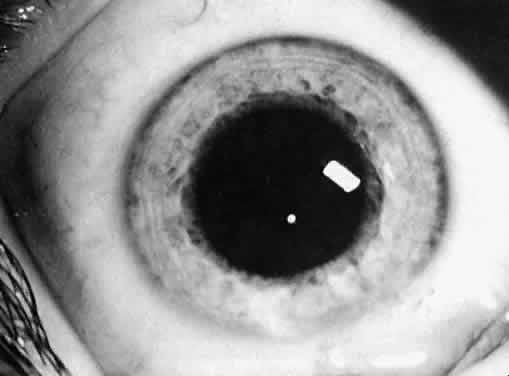

Type and Location

Usually, anterior polar cataracts are visually insignificant and allow normal visual development (see Fig. 1). However, some affect vision, and all require careful monitoring.7 Centrally located cataracts that are on or near the posterior lens capsule have a greater effect on the refraction of light and visual acuity (Fig. 2). Nuclear cataracts associated with metabolic disorders or prenatal infections produce double refracting systems that cause optical distortion and significantly decrease visual acuity (Fig. 3).

Fig. 3. A nuclear cataract present in both eyes of a child with esotropia. The retinoscopy reflex was irregular, and cataract surgery was recommended. Metabolic evaluation and TORCH titer findings were negative.